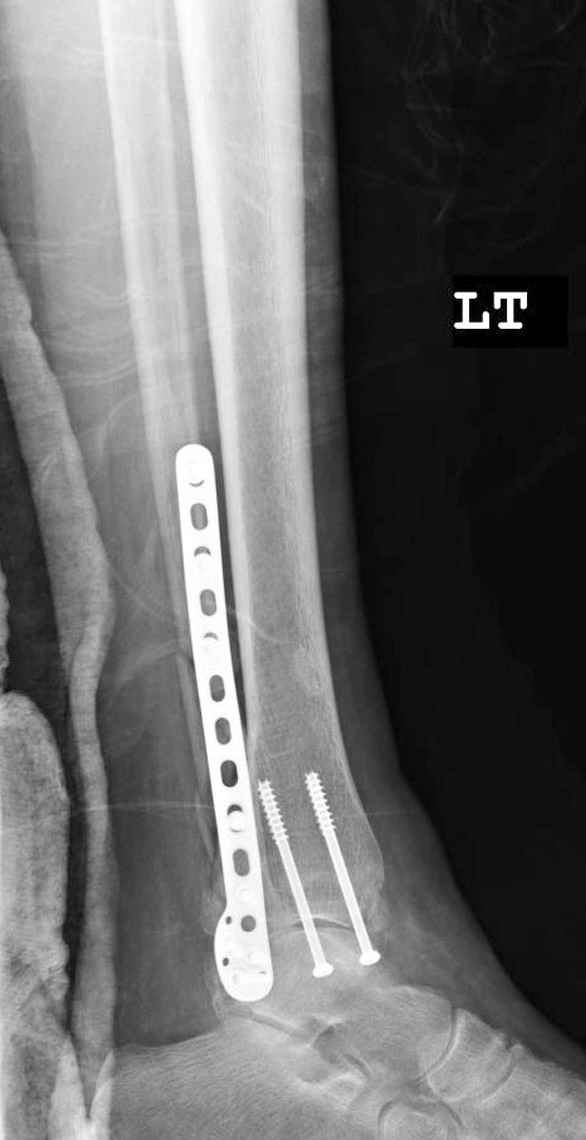

Здесь финальный снимок 73 летней с

сопутствующей шизофренией, латерально бридж

пластину (соединили дистальный конец с диафизом не трогая место перелома) и медиально перкутанно

двумя шурупами. В этам случае без гипса не

обойтись.